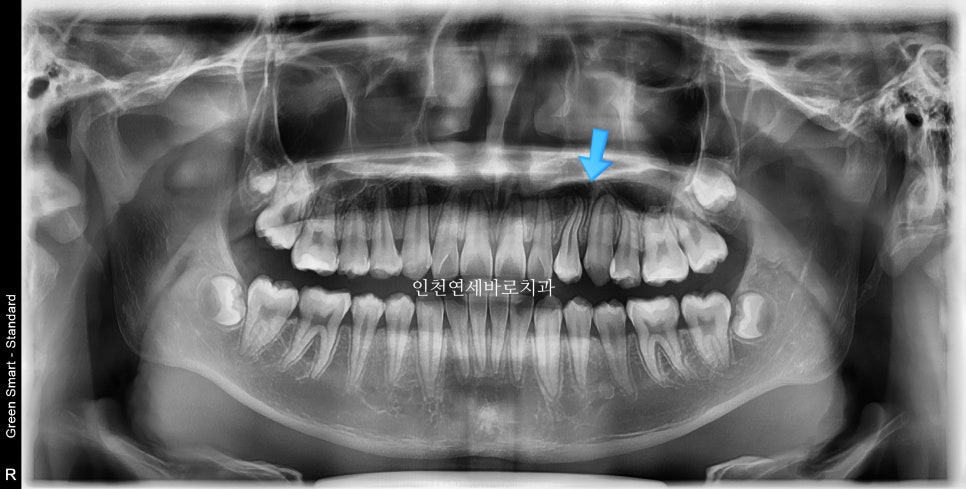

사진상 2 1 3 이라고 표시된 치아의 원래 순서는 1 2 3 입니다.

가끔 이렇게 치아가 만들어지면서 치아의 씨앗 위치가 바뀌면서 뒤죽박죽이 되는 경우가 있습니다.

두번의 계획으로 나눴습니다. 처음 6개월은 1이 내려오기 위한 공간을 만들기.

두번째 세트 제작에서 1을 배열하기로 나눴습니다.

최후방 어금니는 맹출 중 입니다.

화살표 부분의 치아 순서가 일반적인 순서와는 조금 다르지만

기능적, 심미적으로 거의 문제없이 해결했습니다.